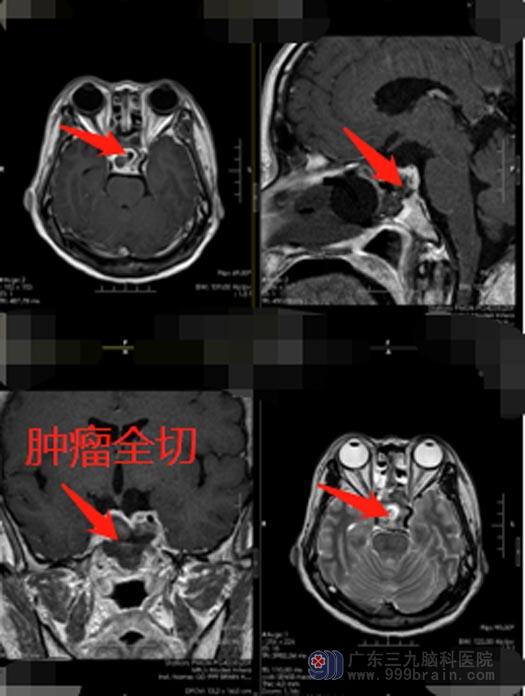

“难怪眼睛越来越看不清”!知道了视力下降的原因后,陈女士欣然地接受手术治疗。完善准备后,由医院副院长、神经外五科鲁明主刀为陈女士施“行经鼻蝶鞍区占位切除术”,经鼻蝶鞍区占位切除术是针对鞍区占位的微创手术方式,利用只有4毫米左右粗的神经内镜进入鼻腔,犹如带有地图一般找到鞍区的脑瘤的位置,再在内镜下将其切除掉。经鼻蝶鞍区占位切除术,作为微创手术方法与传统的开颅手术对比,出血少,痛苦小,风险更低,对患者的创伤小。肿瘤被完整地切除。

术后,陈女士视力明显好转、康复迅速,很快就出院了。